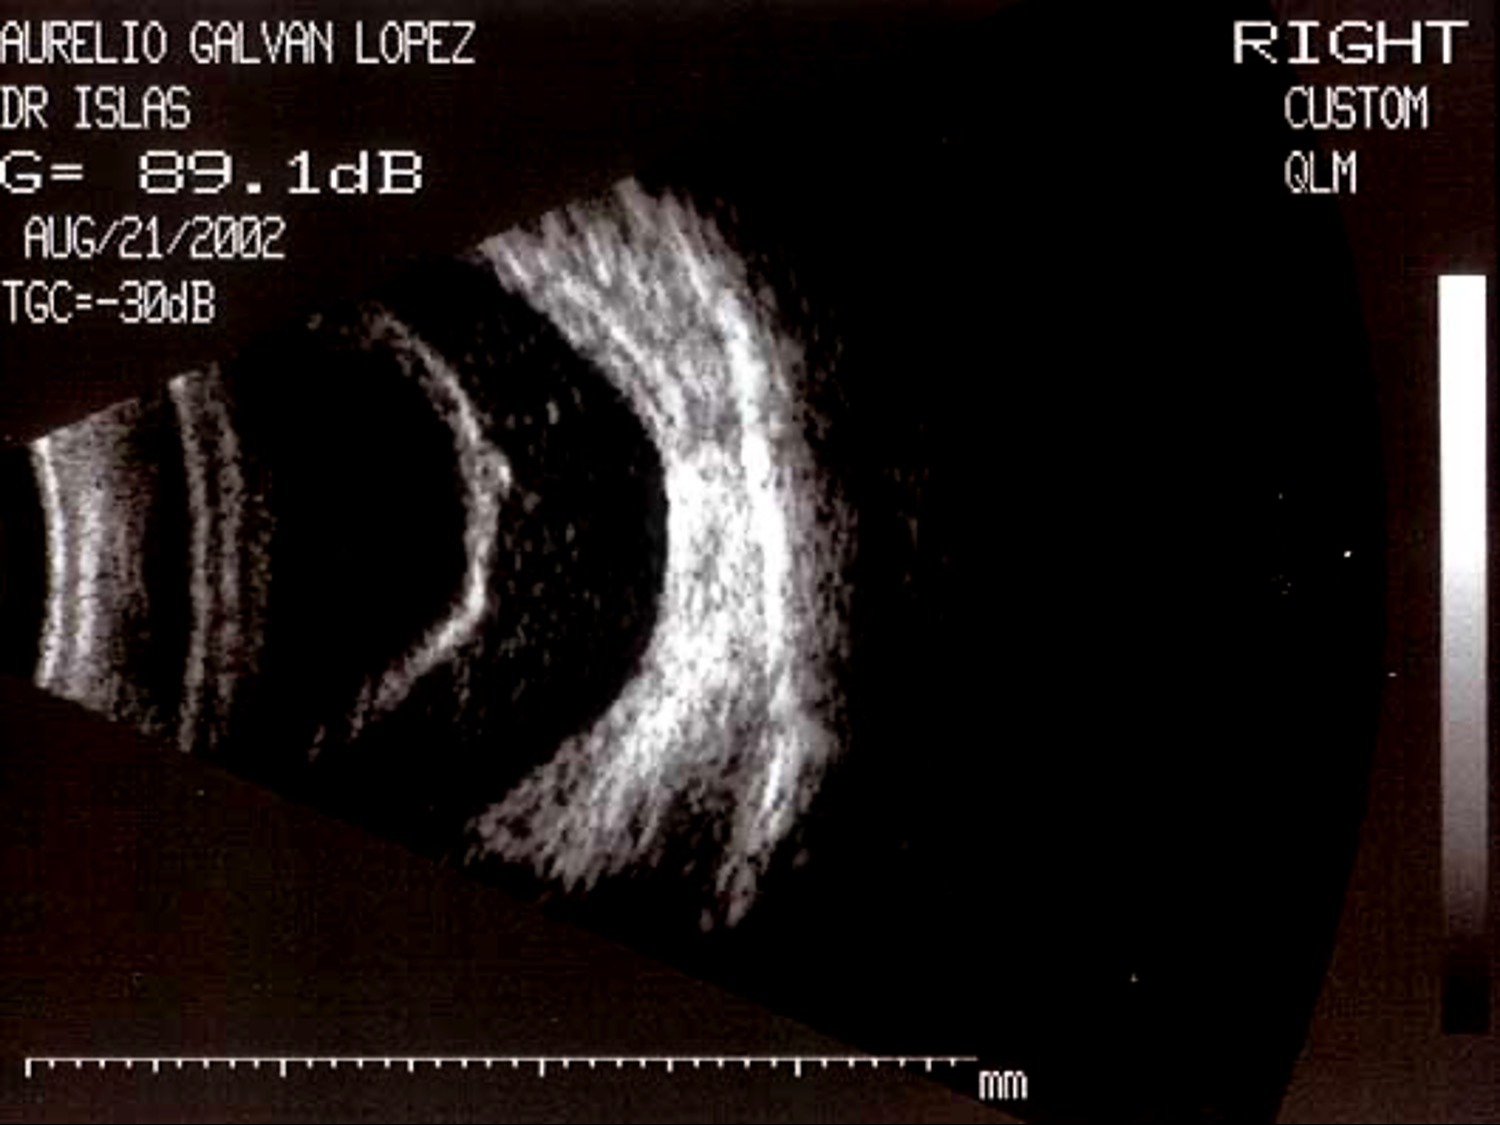

La movilidad del material ecogénico es clave:

Móvil: hemorragia vítrea reciente.

Semimóvil o fija: proliferación fibrovascular.

La inserción del plano de membranas distingue entre DPV y DRT.

El seguimiento permite valorar actividad y evolución del proceso traccional.